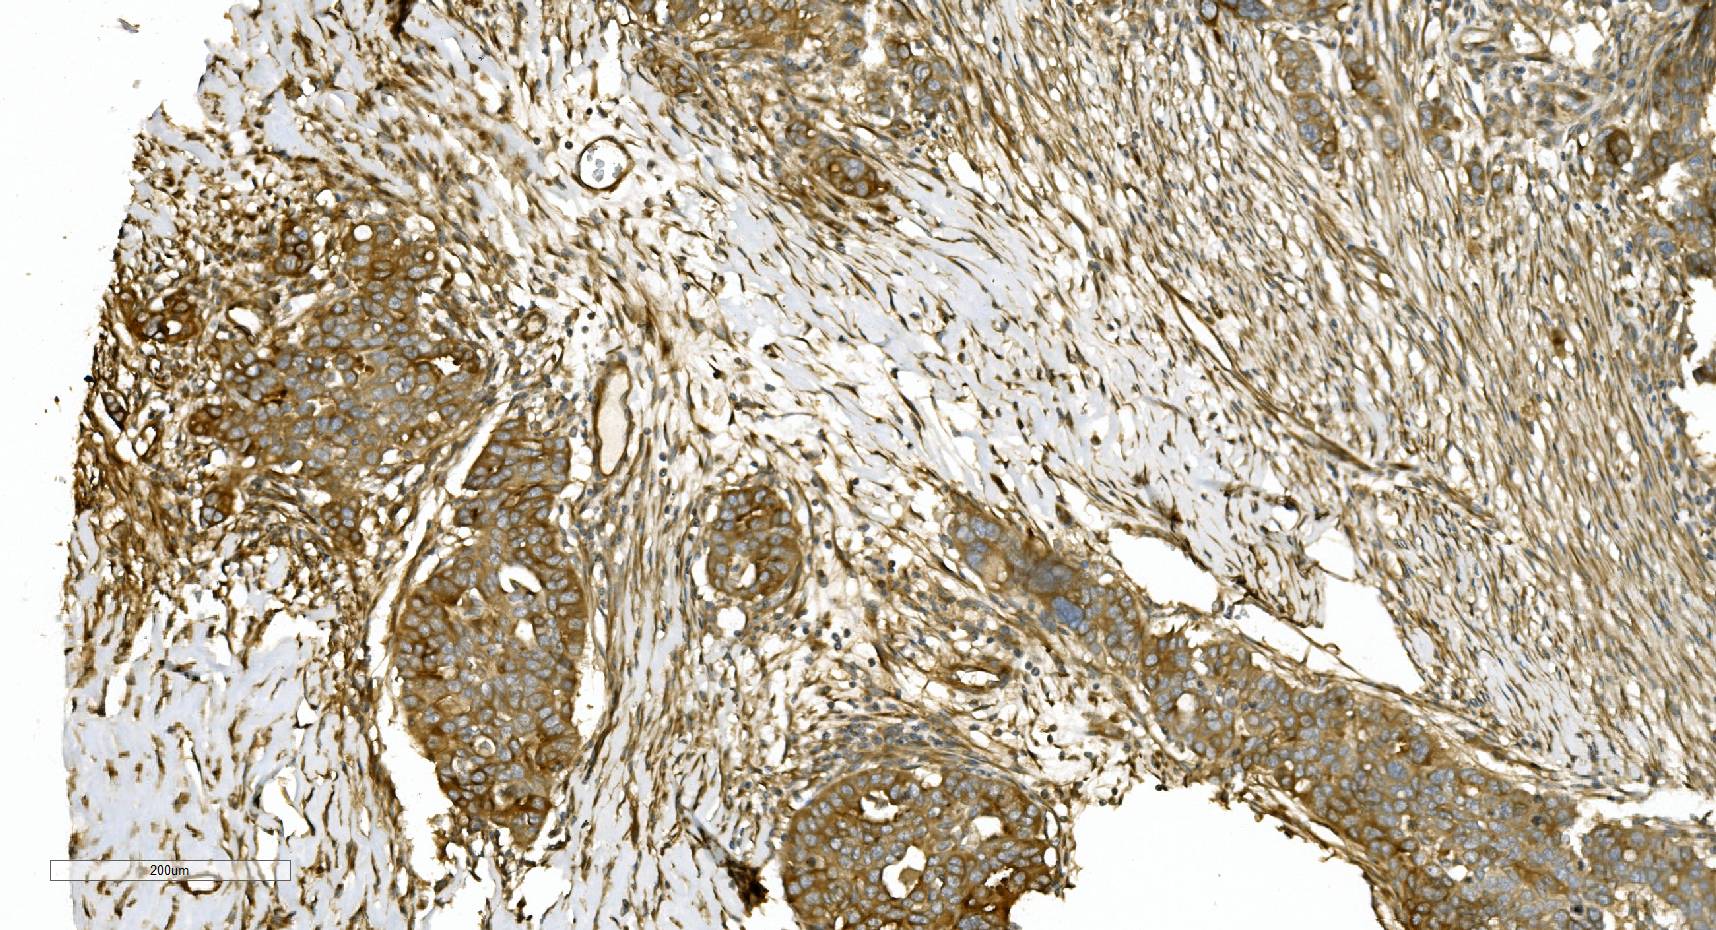

IHC analysis of Alpha Tubulin/TUBA1A using anti-Alpha Tubulin/TUBA1A antibody (M03989-3).

Alpha Tubulin/TUBA1A was detected in a paraffin-embedded section of human ovarian serous adenocarcinoma tissue. Biotinylated goat anti-mouse IgG was used as secondary antibody. The tissue section was incubated with mouse anti-Alpha Tubulin/TUBA1A Antibody (M03989-3) at a dilution of 1:200 and developed using Strepavidin-Biotin-Complex (SABC) (Catalog # SA1021) with DAB (Catalog # AR1027) as the chromogen.